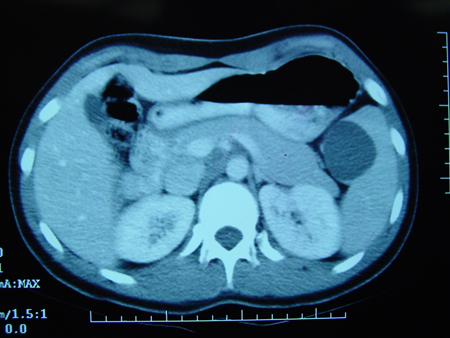

Tomografia computadorizada (TC) revelando cisto cheio de líquido dentro do baço

Do acervo de Dr. KuoJen Tsao; usado com permissão